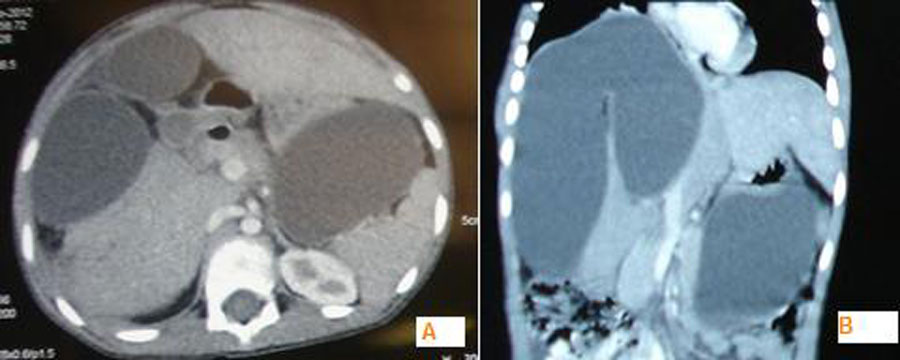

Four weeks later, the patient presented with upper abdominal fullness not associated with any other complaint. He was afebrile and hemodynamically stable. There was no icterus. On examination, there was distension of abdomen limited to the upper half of abdomen. There was no demonstrable free fluid and bowel sounds were normal. Laboratory values were: Hb-9.2 gms/dl, TLC-6900/mm3, serum bilirubin-0.8 mg%, ALT-17 U/ L, ALP 365 U/ L, AST-28 U/ L. Sonography revealed a large multiloculated cystic mass (15cmx13cmx18 cm) antero-superior to the liver. The intra-hepatic biliary radicals and the common bile duct were not dilated.  There was no free fluid. CT scan was done to know further details. It showed 13cmx13cmx16 cm cystic lesion in the right lobe of liver with well defined septa of liver parenchyma within it (Fig. 2). Another cystic lesion was found in the left sub-hepatic space and lesser sac. Based on the findings it was diagnosed to be a “walled off” bile collection.  A pig tail catheter was inserted percutaneously into the bilioma under sonographic guidance which was both diagnostic and therapeutic. It drained about 500 ml of greenish brown fluid overnight and culminated with disappearance of abdominal distension. The catheter was removed after 4 days when the effluent was negligible. Patient was discharged and on follow up 3 weeks later, found to be doing well. Currently patient is on albendazole therapy.

Figure 2: A-Axial section of CT scan showing cystic lesion in the right lobe of the liver with well defined septa of liver parenchyma within it. The lesion in lesser sac is also appreciated B- Same in coronal section